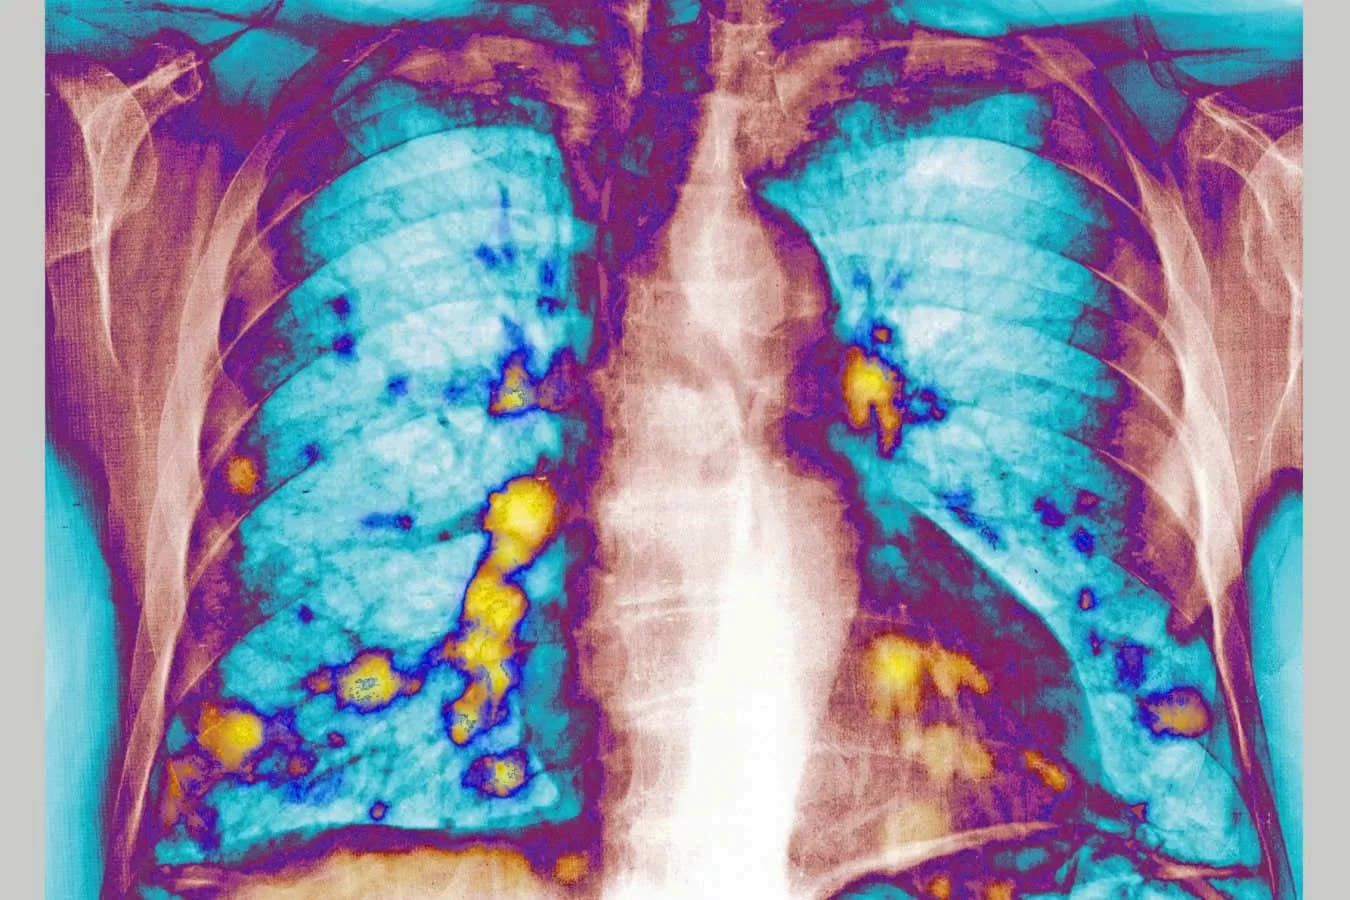

In the study, researchers infected mice with RSV and then injected them with breast cancer cells. They found that the virus triggered the release of proteins that stop viruses from replicating in the lungs. These proteins also made it harder for cancer cells to seed new tumors in the lungs.

The researchers also noted that the effects of RSV on breast cancer cells were specific to the lungs. When they injected the cancer cells into other parts of the body, such as the liver or brain, the virus did not have the same effect. This further supports the idea that RSV could be a potential treatment for preventing lung metastasis in breast cancer patients.